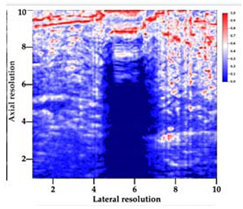

3.3. B-Mode Images

3.5. Echogenicity

4.1. Ultrasonography and Aerogel Dimensional Analyis

| Aerogel Type | US Image | Normalized Intensity Map | 3D Intensity Map | |

|---|---|---|---|---|

| 1 | Muscle |  |  |  |

| 2 | X-silica |  |  |  |

| 3 | X-silica-La2O2S:Eu |  |  |  |

| 4 | SMPU-Mix-14 |  |  |  |

| 5 | SMPU-Mix-18 |  |  |  |

| 6 | BRF-CA |  |  |  |

| 7 | ARF-CA |  |  |  |

| 8 | X-Ca-Alg-2 |  |  |  |

| 9 | X-Ca-Alg-1 |  |  |  |